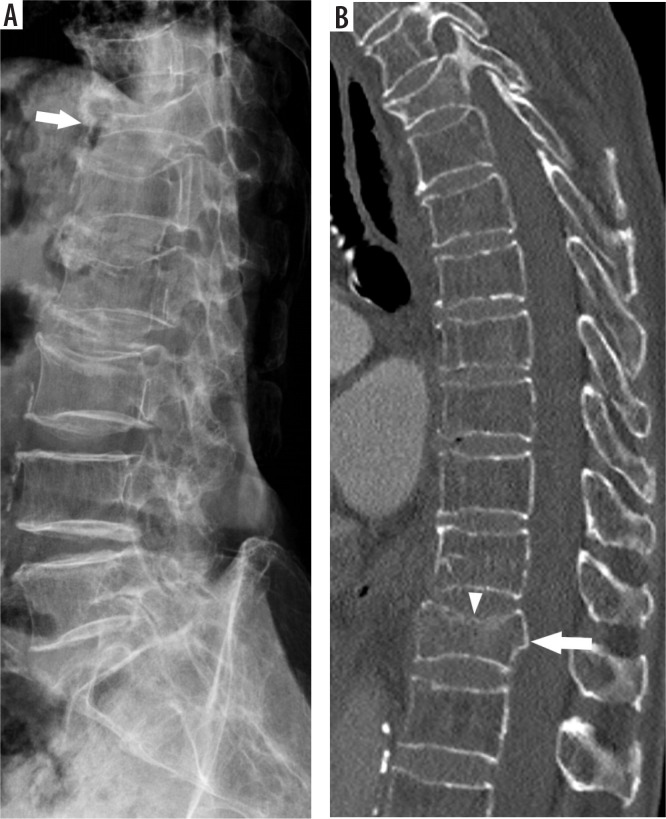

Purpose: To evaluate the diagnostic value of X-ray in detecting acute thoracolumbar (TL) fractures in minor trauma patients, using computed tomography (CT) as the reference standard, and to assess the impact of rigid spine conditions and reader experience on performance.

Material and methods: This retrospective single-centre study included patients with acute TL fractures from minor trauma between July 2014 and December 2020, who underwent both X-ray and CT. On CT, the presence or absence of rigid spine conditions, location, and fracture morphology were assessed. Two independent readers (a radiology resident and an attending radiologist) evaluated the radiographs, blinded to CTs. Sensitivity, specificity, and accuracy were calculated, and interobserver agreement was assessed using Cohen's κ coefficient.

Results: Sixty-three patients (32 with rigid spines, 31 without) with 84 fractures were included. The resident radiologist showed lower diagnostic accuracy than the attending radiologist, with more false positives in the rigid-spine group. In both groups, unrecognised fractures were more common for the resident radiologist (61.2% in rigid-spine patients and 48.6% in non-rigid-spine patients) compared to the attending radiologist (51.0% and 40.0%, respectively). Thoracic fractures were more frequently missed than lumbar fractures. Interobserver agreement was moderate (κ = 0.44) in the rigid-spine group and substantial (κ = 0.67) in the non-rigid-spine group.

Conclusions: Radiographs cannot reliably exclude unstable TL fractures in minor trauma patients. Attention should be paid to the lower thoracic region when evaluating lumbar radiographs.